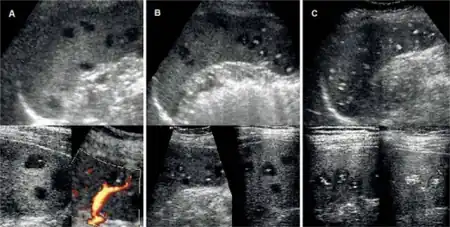

Peliosis hepatis

B. henselae is the cause of peliosis hepatis, which is defined as a vascular proliferation of sinusoid hepatic capillaries resulting in blood-filled spaces in the liver in HIV patients and organ transplant recipients. Peliosis hepatis can be associated with peliosis of the spleen, as well as bacillary angiomatosis of the skin in HIV patients.[22]